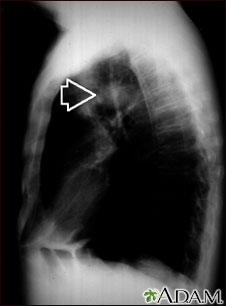

Masa pulmonar - Vista lateral de la radiografía de tórax

La parte superior del pulmón de este individuo presenta una masa. Aunque la causa puede sospecharse de acuerdo con los antecedentes de esta persona, existen muchas enfermedades que pueden producir lesiones pulmonares.